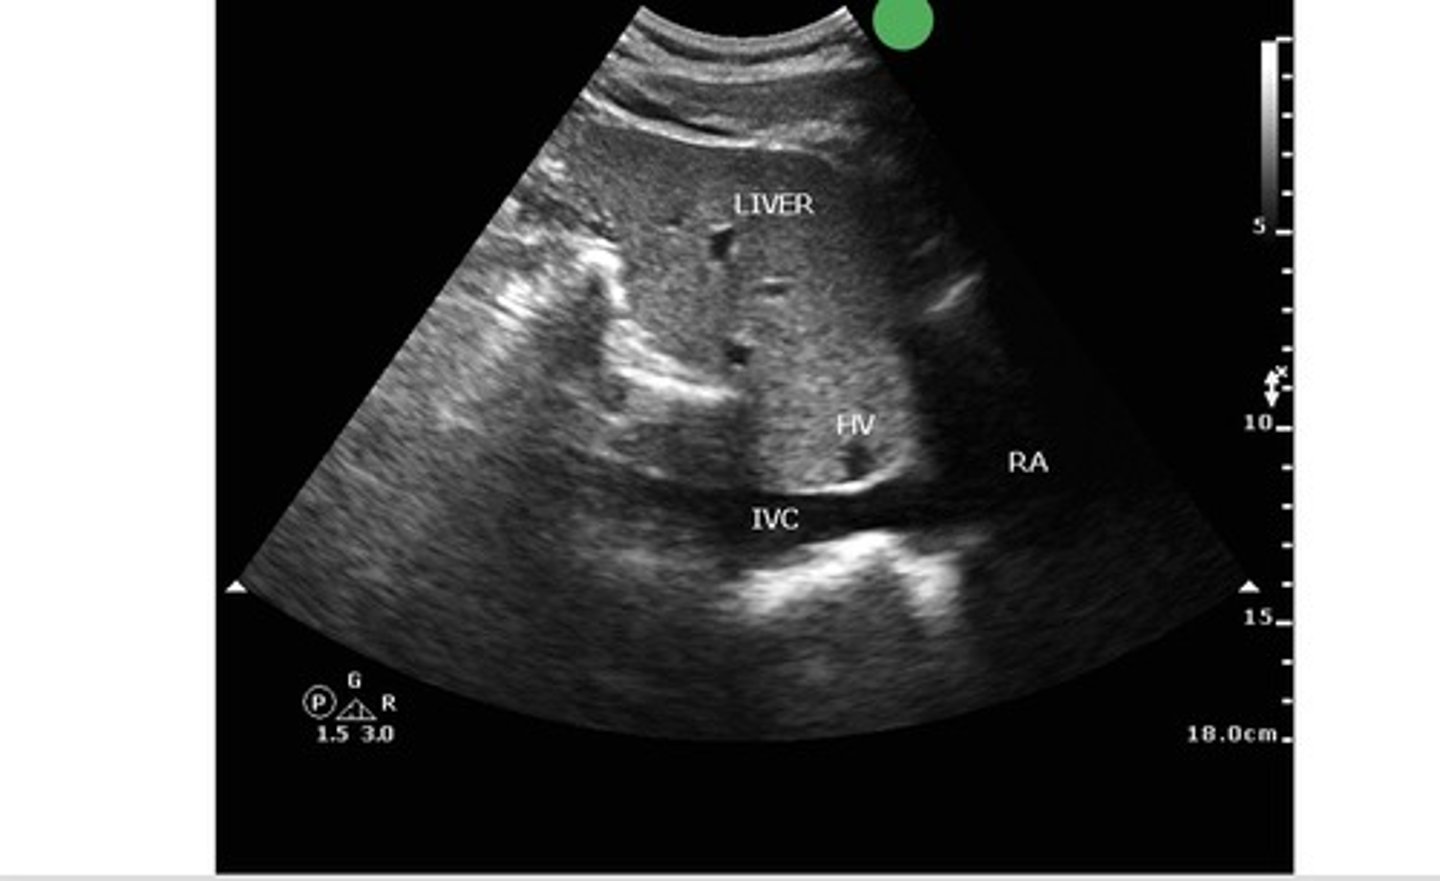

subxiphoid IVC view

what view is this?